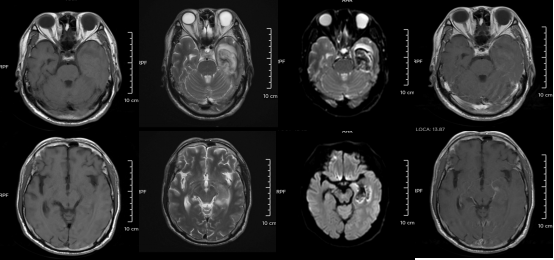

△某單純皰疹病毒性腦炎患者的醫(yī)學(xué)影像。圖源:浙江大學(xué)醫(yī)學(xué)院附屬第二醫(yī)院

但如果拖延治療,甚至?xí)l(fā)腦炎,可能出現(xiàn)癲癇、肢體偏癱、尿潴留、認(rèn)知功能障礙等嚴(yán)重后遺癥,恢復(fù)時間長達(dá)3-6個月,甚至影響終身。